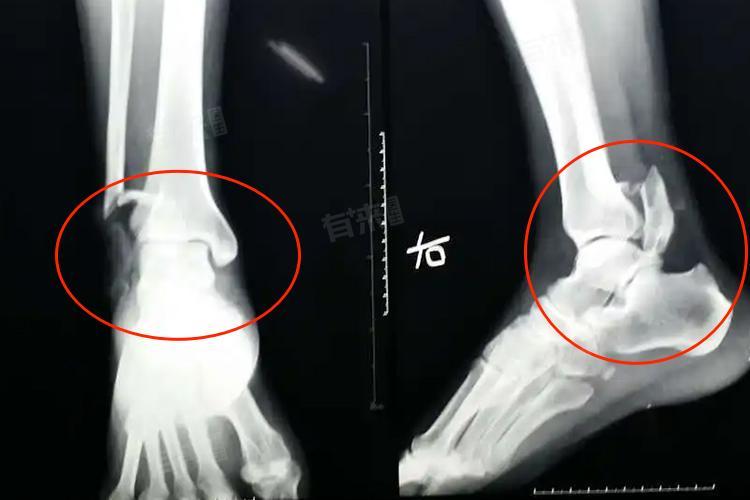

脚踝粉碎性骨折后正常走路时间取决于骨折严重程度、治疗方式、年龄、康复锻炼及营养状况等,大致在3-7个月不等,患者应积极配合医生进行治疗与康复。

1、骨折严重程度:若骨折情况复杂,粉碎程度高,伴有明显的移位等,恢复时间较长,严重的脚踝粉碎性骨折可能需要4-6个月,这是因为复杂的骨折需要更精细的手术复位和更长时间的固定,以确保骨折部位稳定愈合。